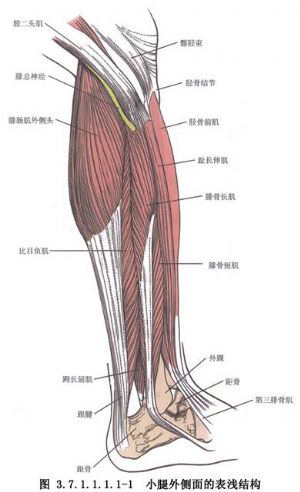

脛骨幹骨折不癒合有多種手術治療方法,需要根據骨折不癒合的類型、骨折對位對線及軟組織情況予以選擇。但要注意儘量選用方法較簡單,創傷小和局部血循環破壞少的手術。脛骨幹骨折影像表現及解剖見下圖(圖3.7.1.1.1.1-0-5~3.7.1.1.1.1-0-8)。